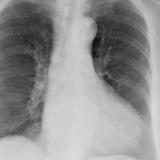

Case 9 Thymoma PA

Date: 04/04/2010

Views: 3255